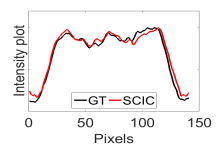

The calculated correlation coefficient (), SNR, as well as CNR values for all tested methods in the synthetic phantom experiment are shown in Table II. As seen in Table II, the proposed NCBC method achieved the highest , CNR as well as SNR values when compared to that of other tested methods. Visual results from the bias-corrected DW-MR synthetic phantom data produced using different tested methods is shown in Fig. 2(c-i). It can be observed that the MCBC, LEMS, and proposed NCBC method were able to achieve the best level of bias correction when compared to the other tested methods. This is particularly apparent in the peripheral zone (PZ) of the prostate gland as highlighted using red ROIs in Fig. 2(a-i), where intensity inhomogeneities are still present to a significant degree in the bias-corrected phantom data produced using the LS, SCIC, SGD and BCFCM methods, while strong inhomogeneity correction performance is achieved using MCBC, LEMS, and the proposed NCBC method. Furthermore, it can be observed that NCBC exhibited minimal intensity inhomogeneities when compared with MCBC and LEMS, particularly in the area that is highlighted using Red ROIs. To better represent the outperforming of proposed NCBC method in terms of bias correction using synthetic phantom, the data intensity profiles corresponding to the drawn blue line in Fig. 3(a) are shown in Fig. 3(b) for uncorrected data (red color plot) versus ground truth data (black color plot) and in Fig. 3(c-i) for corrected data using different tested methods (red color plots) versus ground truth data (black color plots). As the intensity profiles of Fig. 3(b-i) show, NCBC method was resulted in an intensity profile with the most flatness and less amount of variation compared to the intensity profiles of uncorrected image as well as reconstructed images using other tested methods as such confirms the better performance of proposed NCBC method in terms of bias field correction.